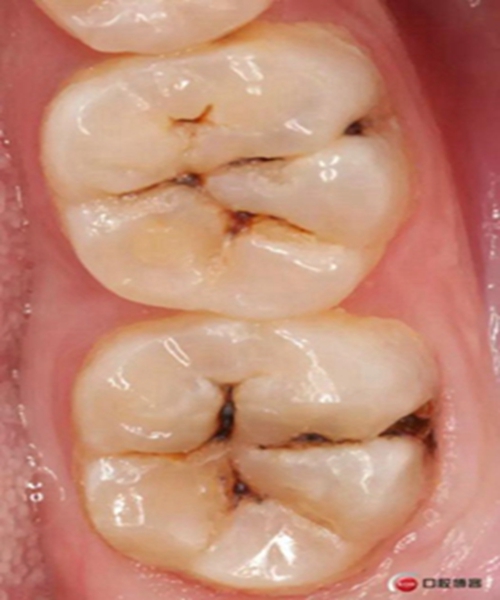

左下后牙樹脂充填一例 科貿(mào)嘉友收錄

這兩顆牙都是單色充填,用的3M家的P60,然后進行了窩溝染色,對于后牙來講很多時候單色就已經(jīng)足夠了,因為畢竟美觀要求不是太高,功能才是最重要的,另外如果真的要用不同顏色的樹脂進行分層的話建議本質(zhì)用飽和度稍高一些的牙本質(zhì)樹脂,這樣堆塑出來的效果能好一些 。